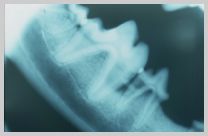

"Favourable" fracture

of mid body of mandible with fracture running from caudo-dorsal

to rostro-ventral